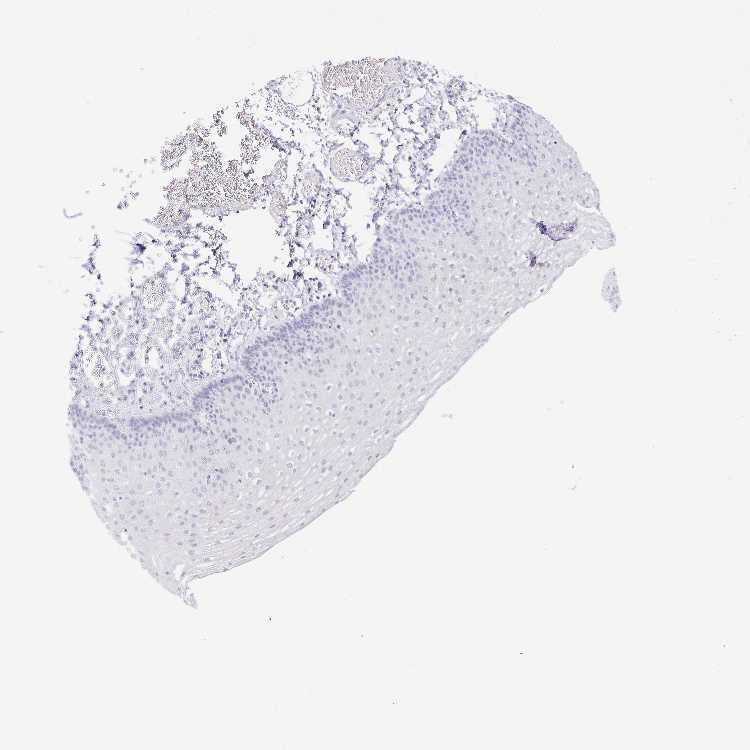

ESOPHAGUS - Antibody stainingi

Antibody staining in the annotated cell types in the current human tissue is reported as not detected, low, medium, or high, based on conventional immunohistochemistry profiling in selected tissues. This score is based on the combination of the staining intensity and fraction of stained cells.

Each image is clickable and will lead to virtual microscopy that enables deeper exploration of all samples and also displays staining intensity scores, fraction scores and subcellular localization as well as patient and tissue information for each sample.

Antibody HPA051904Antibody HPA055804

Squamous epithelial cells MediumNot detected